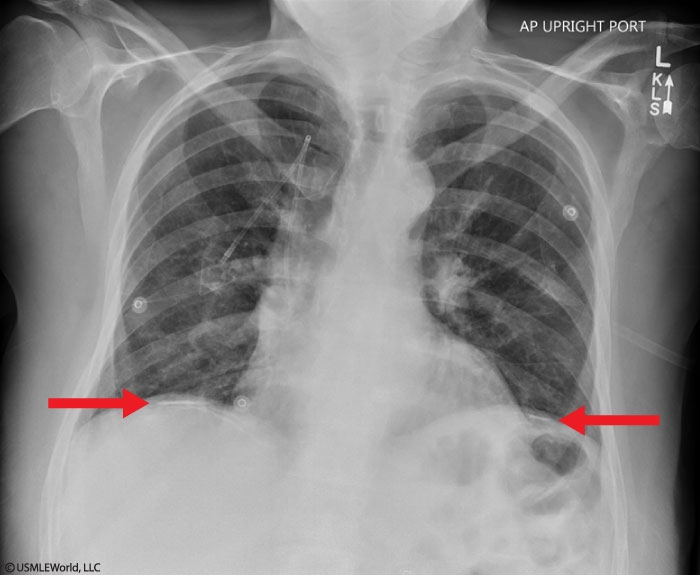

Asbestosis

Asbestosis and bronchogenic carcinoma can present similarly, with most patients developing progressive dyspnea. However, patients with asbestosis can be asymptomatic for up to 20-30 years after asbestos exposure. Cough, sputum production, and wheezing are not typically present (unless there is concurrent chronic obstructive pulmonary disease). Physical examination frequently shows bibasilar, end-inspiratory crackles and fingernail clubbing as the disease progresses. Chest x-ray can show bibasilar reticulonodular infiltrates, honeycombing (cystic areas surrounded by interstitial infiltrates), and bilateral pleural thickening. High-resolution chest computed tomography typically shows subpleural linear densities and parenchymal fibrosis. Almost 50% of patients have pleural plaques, which can help differentiate asbestosis from other causes of pulmonary fibrosis. Imaging studies may also show signs of bronchogenic carcinoma.